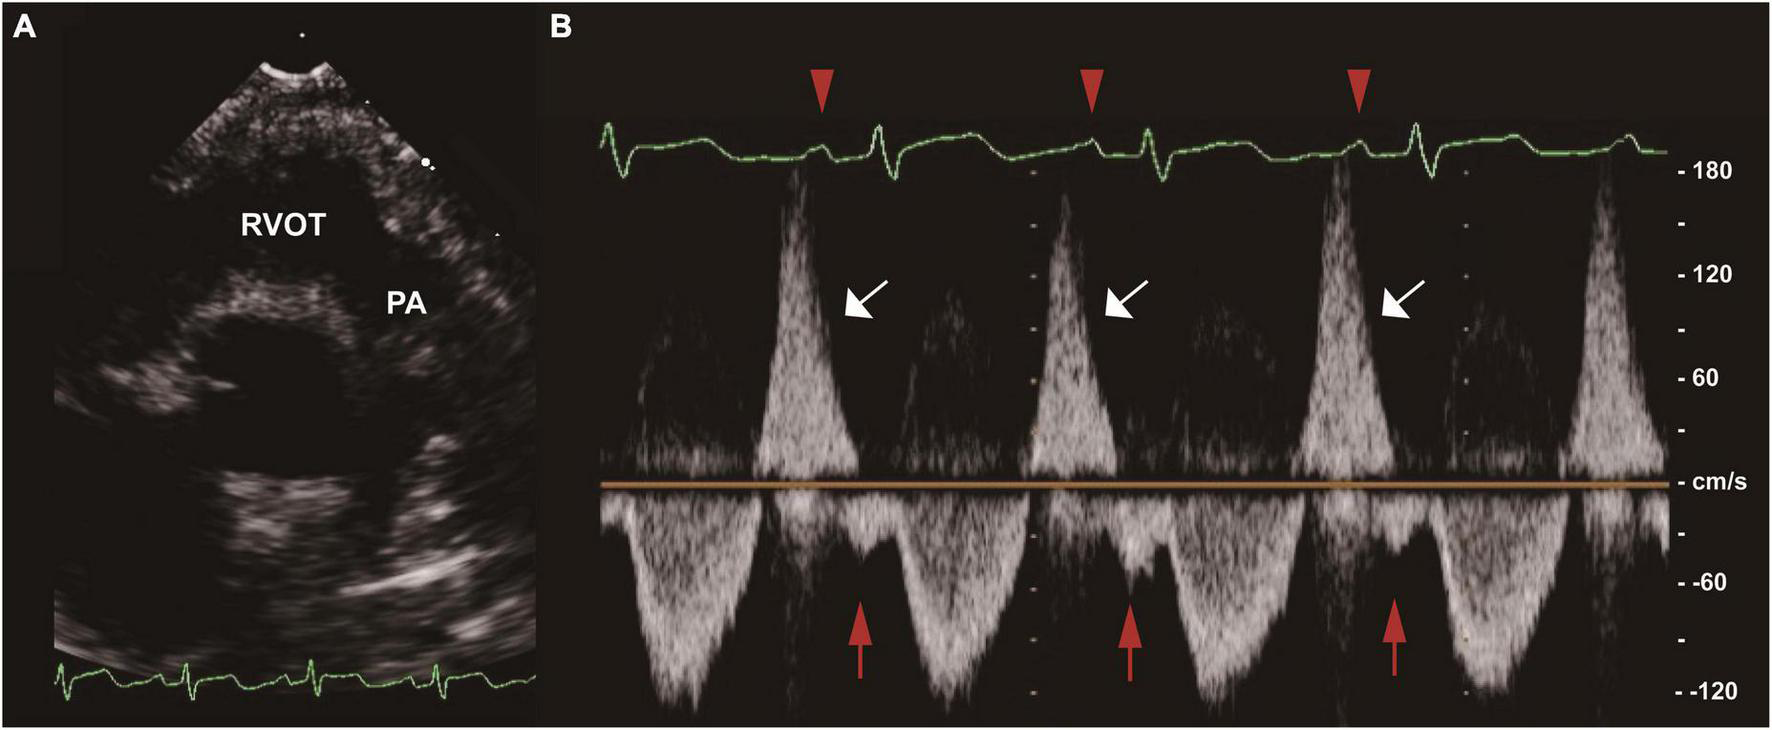

Two-dimensional, M-mode and Doppler echocardiography were performed according to standard American Society of Echocardiography (ASE) guidelines (12, 13). The severity of PR was graded as normal, mild, moderate, and severe based on standard assessment by comprehensive echocardiogram (14). To simplify the analysis, the aforementioned six grades were combined into normal, mild, moderate and severe. Offline measurements of pulmonary artery pulsewave Doppler (parasternal long axis) were performed in all patients by an experienced sonographer before discharge (median time since surgery 7 days [IQR 5]), who had no prior knowledge of the study participants. In order to mitigate the effect of respirophasic variation, pulmonary arterial EDFF was considered to be present if identified in 3 consecutive cardiac cycles (Figure 1). All data in units of length or area were indexed to body surface area (BSA). Vasoactive-inotrope score (VIS) was calculated daily as per Gaies et al. (15), where VIS = dopamine dose (μg/kg/minute) + dobutamine dose (μg/kg/minute) + [100 × epinephrine dose (μg/kg/minute)] + [10 × milrinone dose (μg/kg/minute)] + [10000 × vasopressin dose (units/kg/minute)] + [100 × norepinephrine dose (μg/kg/minute)].

FIGURE 1

End-diastolic forward flow (EDFF) in a patient after tetralogy of Fallot (TOF) repair. (A) Two-dimensional image of the RVOT and PA in the parasternal long axis view. (B) Pulse wave Doppler of the main PA showing pulmonary regurgitation (white arrow) and late diastolic pulmonary artery forward flow (red arrow), a low velocity forward flow immediately following the p wave of the electrocardiogram (red arrowhead) and preceding the systolic forward flow. EDFF, end-diastolic forward flow; PA, pulmonary artery; RVOT, right ventricular outflow tract; TOF, tetralogy of Fallot.